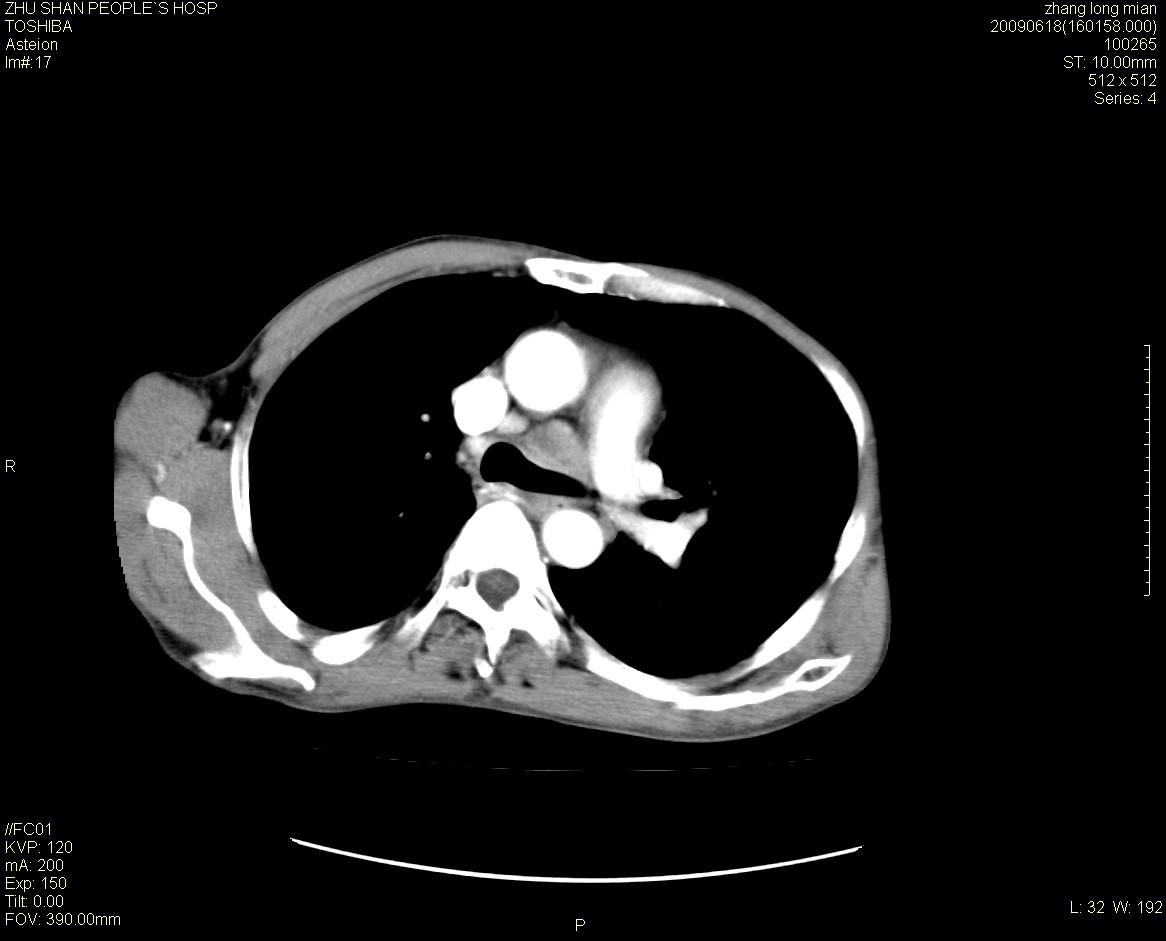

男性 65岁 胸片发现右下肺包块.诊断肺ca并纵隔转移没有问题吧!

增强见纵隔区气管隆突上下及左肺门区肿大淋巴结。左肺感染性病灶。

右下肺见浅分叶状软组织块影,边缘有毛刺,其下部似见不完整偏心空洞影,邻近胸膜凹陷征,并胸腔积液。